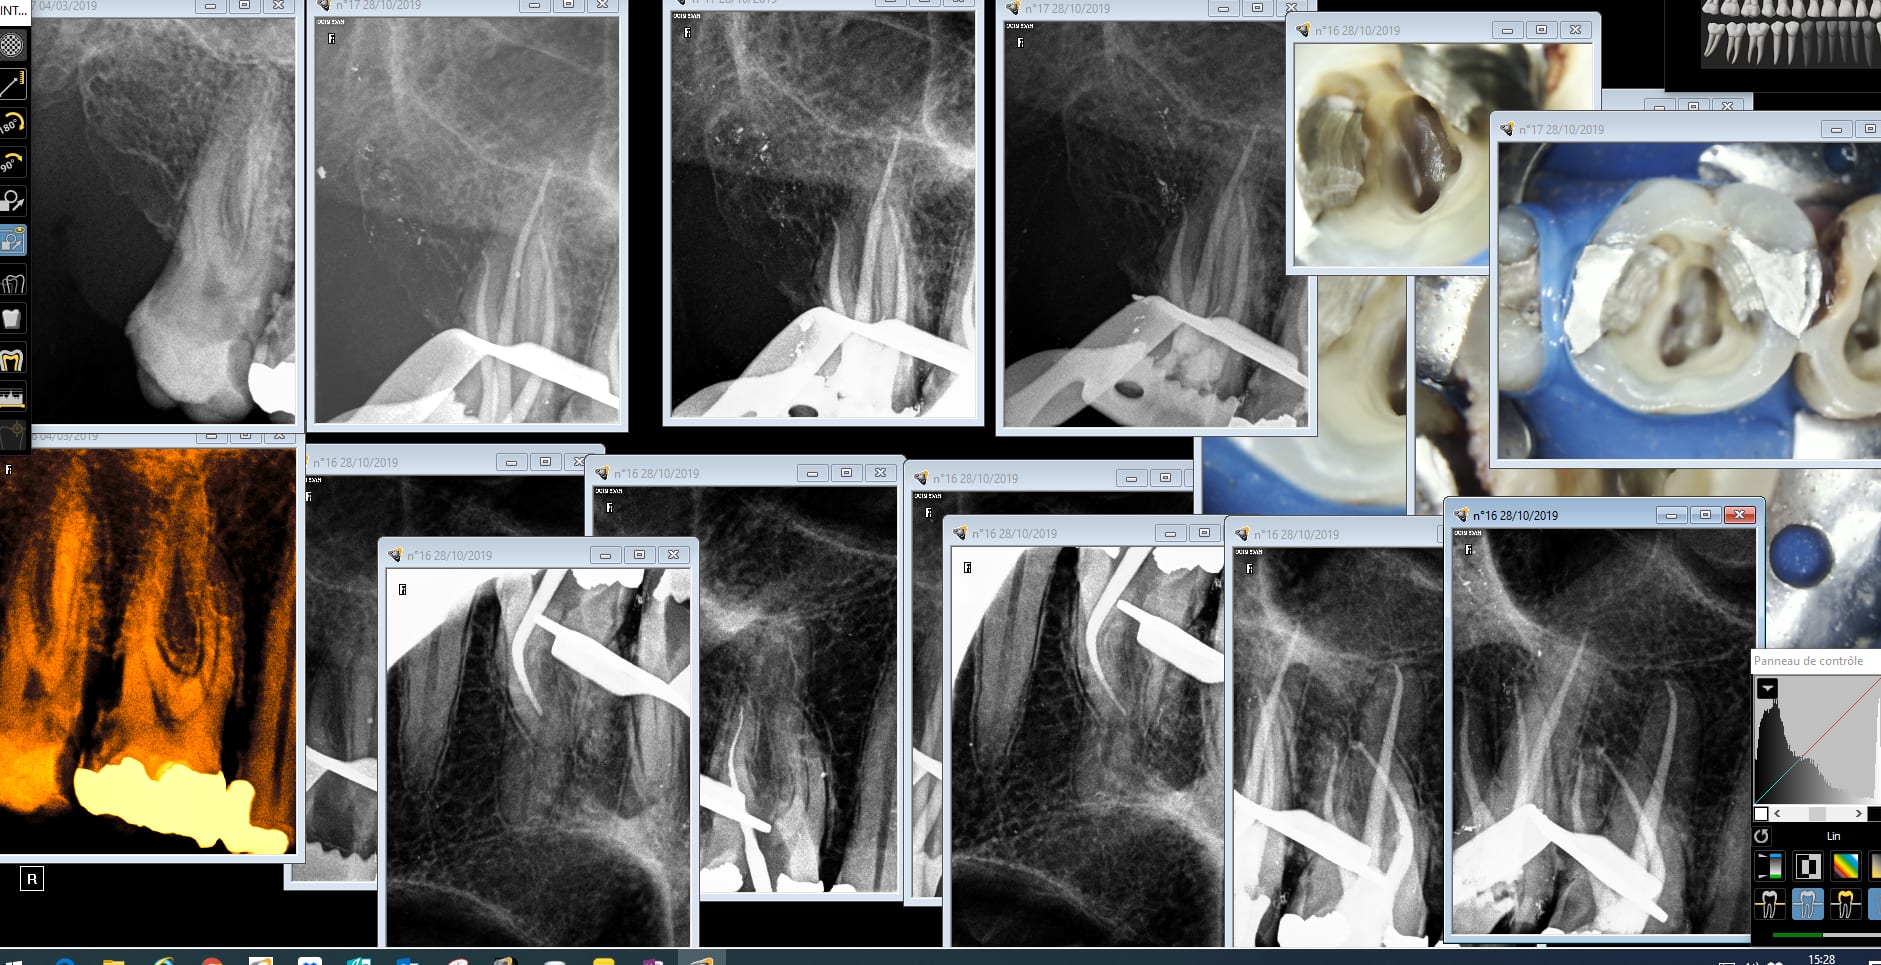

Turp endo 17 16 osaxwp - Eugenol

6szjws718sv1jksw54v4mpj3a6cu - Eugenol

vulpi

28/10/2019 à 17h45

C'est exactement cela, mettre la digue est un acte d'égoïste, on la pose d'abord pour soi.

Pour le MV2 je mets du rap, tu devrais essayer Chicot😁